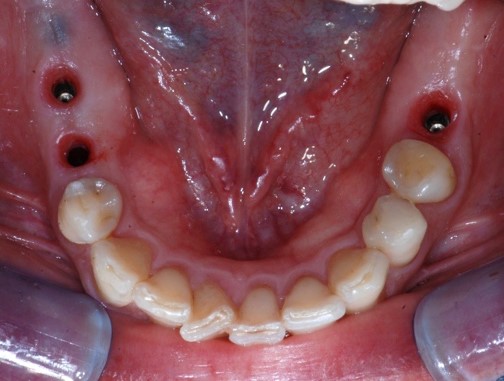

Fig. 9. Controllo a 3 mesi di distanza dall’intervento.

Passato un periodo di circa 3 mesi per la corretta osteointegrazione degli impianti, si procedeva con le fasi di protesizzazione (Figura 9).